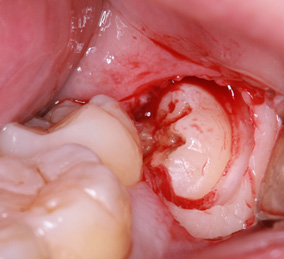

親知らずの抜歯(2回法)

親知らずの歯根の先端と下顎神経が近接している場合は2回に分けて抜歯を行うことがあります。まず、親知らずを2分割して頭の部分を抜きます。その後しばらく期間をおいて、のこる歯根の部分が頭を抜いたスペースに移動したのを確認して抜きます。

このように2回に分ける事で安全な抜歯が可能です。

※歯肉の切開、出血を伴う写真がございます。

まず歯冠を切除し、疼痛がでないよう、冠部歯髄を除去してネオダイン(歯髄の鎮痛鎮静、象牙質の消毒、覆髄)を填入します。その後、粘膜骨膜弁にて完全閉鎖を行います。以下に処置の流れを示します。